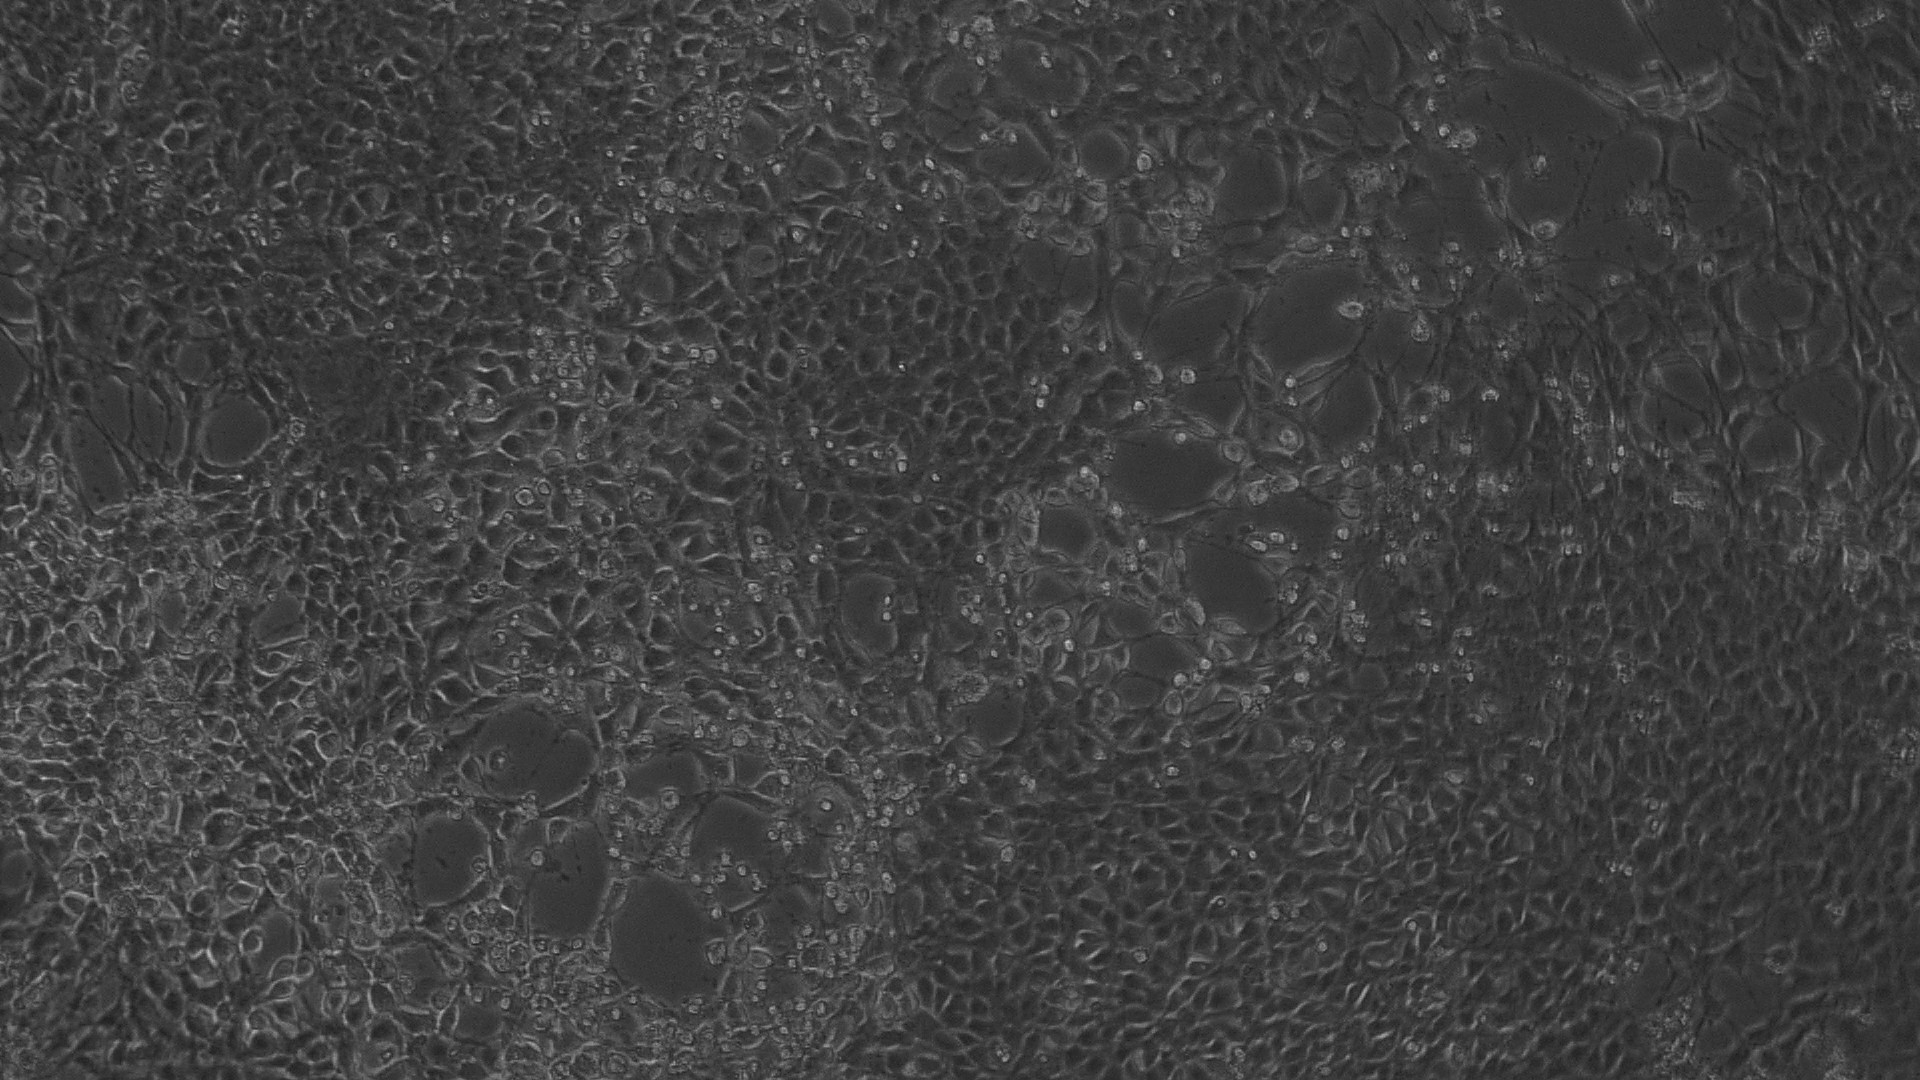

Antiproliferative effect by direct microscopic observation

The entire plate was observed at an interval of every 24 h; up to 72 h in an inverted phase-contrast tissue culture microscope (Labomed TCM-400 with MICAPSTM HD camera) and microscopic observations were recorded as images. Any detectable change in the morphology of the cells, such as rounding or shrinking of cells, granulation, and vacuolization in the cytoplasm of the cells, were considered as indicators of cytotoxicity.

In vitro anti-cancer activity

In vitro anticancer actiivity of ethanolic extract of leaves of Pothos scandens Linn. was evaluated against HeLa and MCF 7 cell lines. The viability of cells was evaluated by direct observation of cells by an Inverted phase contrast microscope and MTT assay method. The morphological changes in HeLa and MCF 7 cells after treatment with the extract and standard doxorubicin are shown in fig. 5, 6, 7 and 8. The IC50 values are shown in table 4.

According to the American National Cancer Institute (NCI), crude extracts with an IC50<30 μg/ml are considered to be active against cancer cells [32, 33]. Different concentrations of the ethanolic extract of leaves of Pothos scandens Linn. exhibited potent cytotoxic activity against HeLa and MCF 7 cell lines with IC50 of 22.9 and 18.32 μg/ml, respectively.

Fig. 7: Morphological changes showing inhibition of MCF 7 cell lines by different concentrations of ethanolic extract of leaves of Pothos scandens. a: -ve control (95% ethanol), b: 6.25 µg/ml, c: 12.5 µg/ml, d: 25 µg/ml, e: 50 µg/ml f: 100 µg/ml